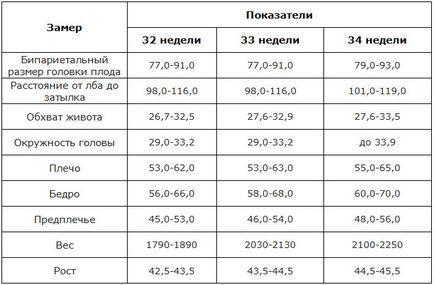

norme fetometry

Indicatori de norme din SUA care spun despre mărimea fătului:

Interpretați rezultatele nu ar trebui să sonolog medic și un obstetrician-ginecolog, o sarcina de conducere. În cazul în care parametrii sunt măsurate în copilul, nu respectă în totalitate cele de mai sus, asigurați-vă că pentru a vorbi cu ea, fără a pune ei pe cont propriu nu sunt diagnostice. Nu uitați: fiecare copil - este diferit, principalul lucru care a fost performanța normală a organelor sale interne.